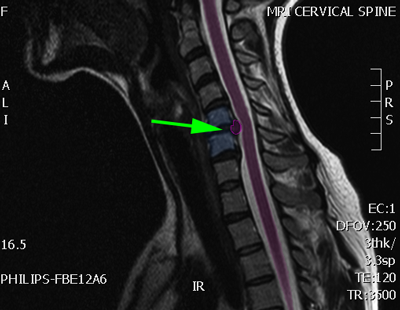

Ασθενής με αυχενική μυελοπάθεια, λευκή περιοχή στο νωτιαίο μυελό (πράσινο βέλος)

Ασθενής με αυχενική μυελοπάθεια, λευκή περιοχή στο νωτιαίο μυελό (πράσινο βέλος)